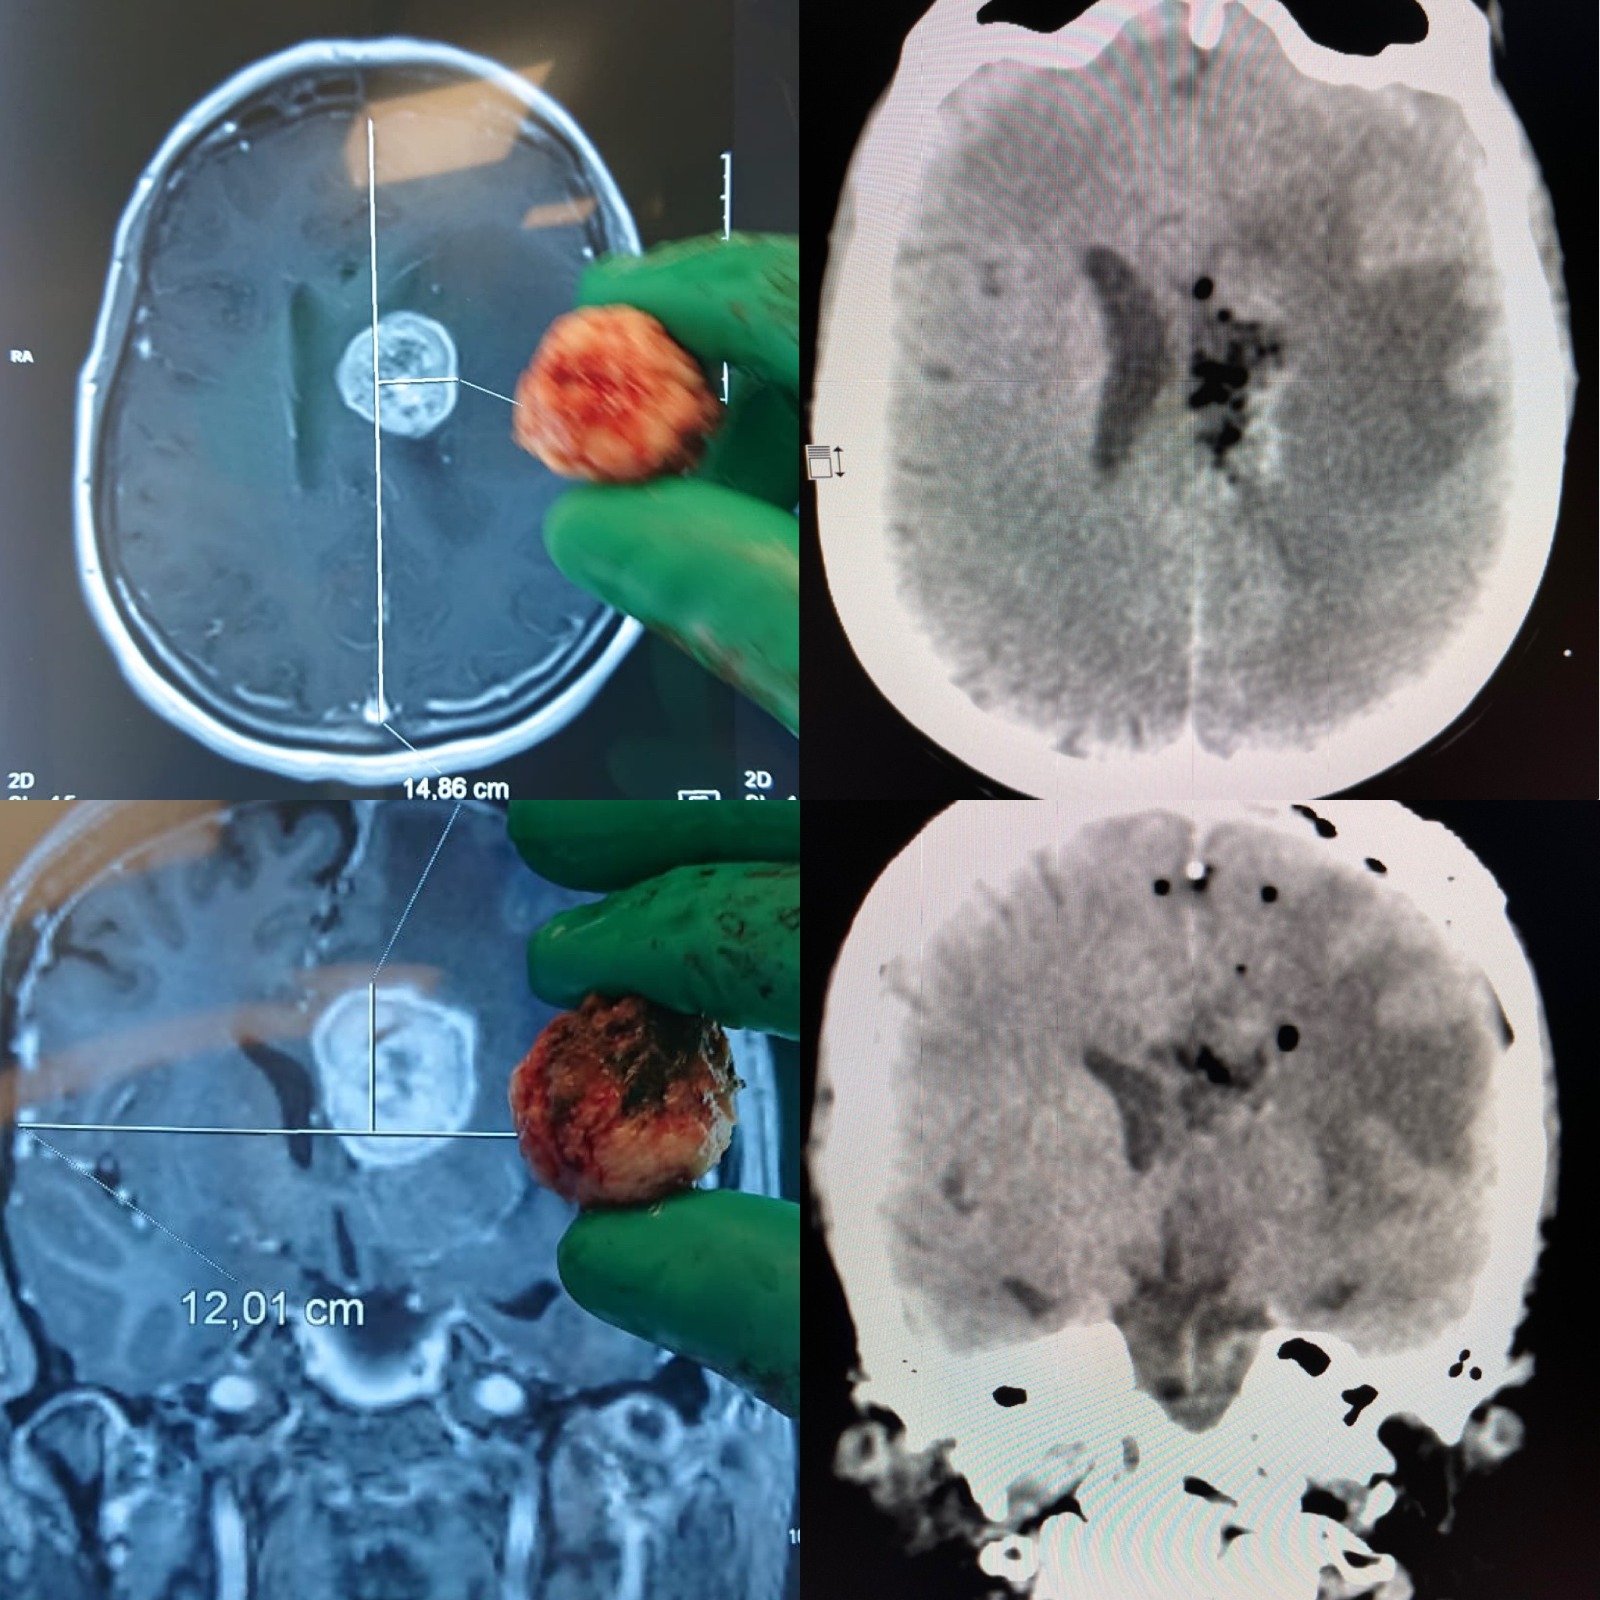

Cirugía de Tumores Cerebrales

Resección con neuronavegación y monitoreo neurofisiológico intraoperatorio para máxima seguridad.

Seguimiento oncológico integrado para pacientes con gliomas, meningiomas y metástasis cerebrales.